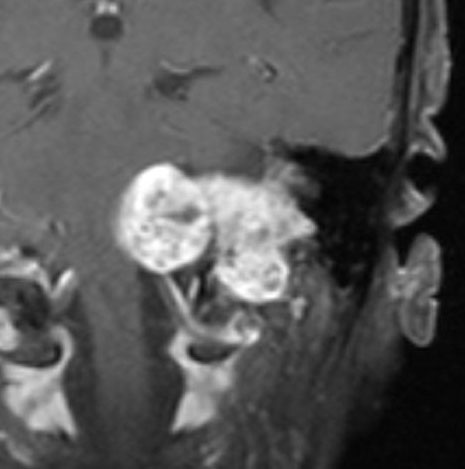

症例:小脳延髄角槽のもの,頸静脈孔へ少し入るもの

30歳くらいの女性に発生した無症状のものです。矢印のように拡大した頸静脈孔へ少し入っています。定位照射でもよかったかもしれませんが,若い女性なので手術しました。

脳槽部迷走神経根から発生したと考えて,外側後頭下開頭で摘出しましたが,予想外に延髄に近い部分の迷走神経から剥がせず,ほんの少し神経根の上に残しました。術後10年経ちますが腫瘍再燃はありません。聴神経腫瘍で顔面神経の上に薄く腫瘍を残すのと同じ考え方です。